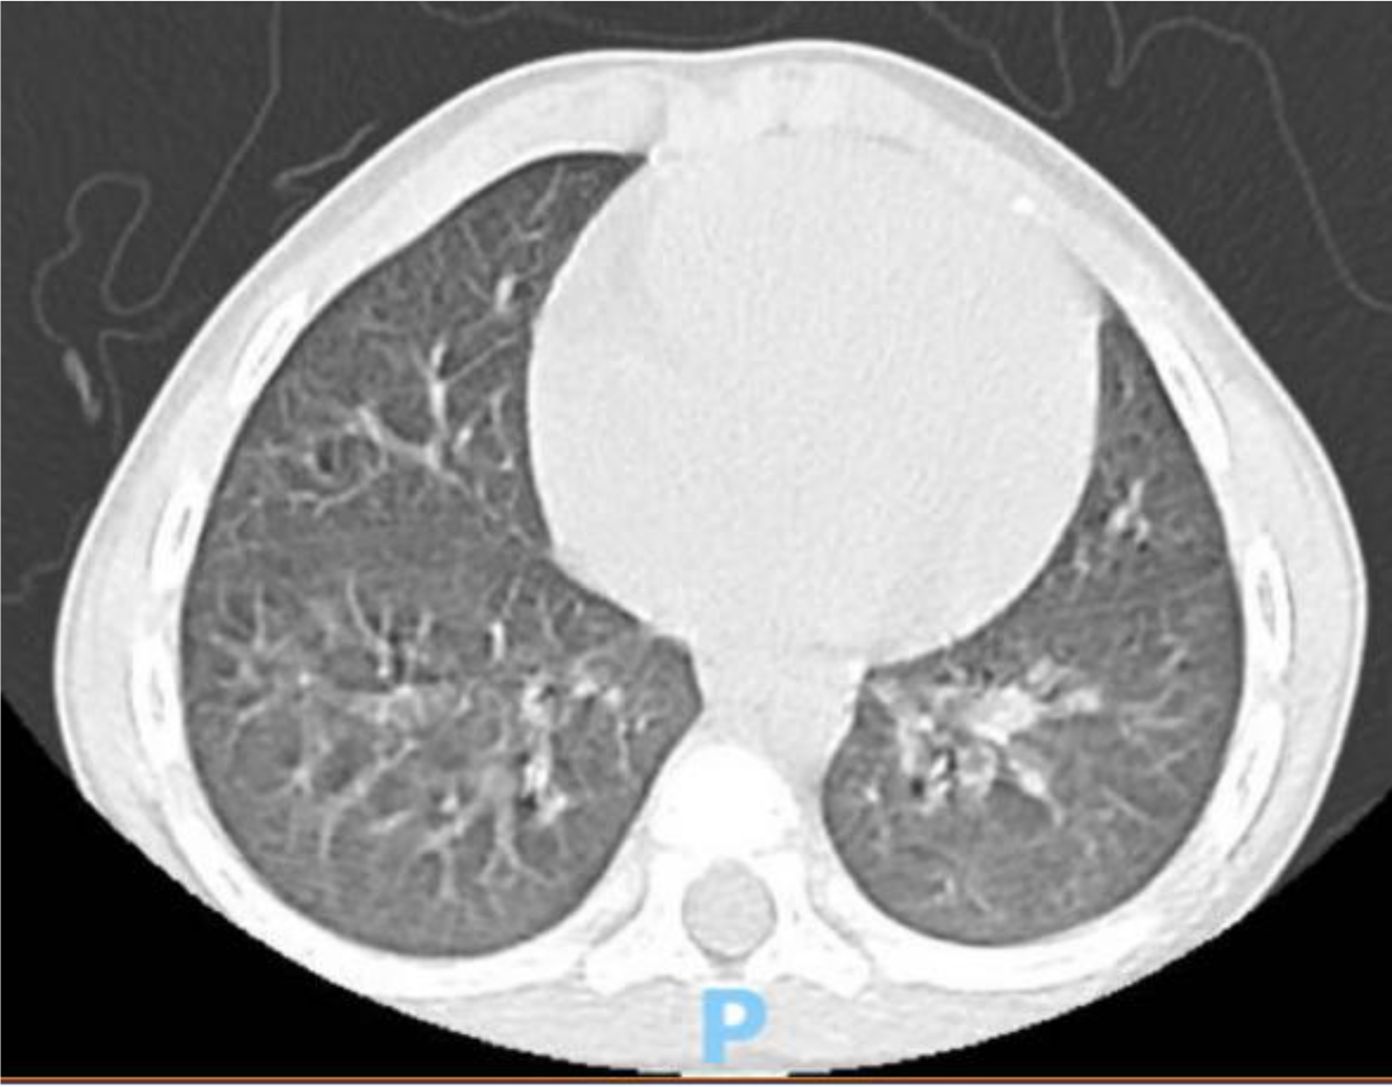

A 4 year-old male was diagnosed with HbE/Beta-thalassemia at age 2 years, and had received monthly red blood cell transfusions since. He was found to have a fully matched sibling and was scheduled for HSCT. At pre-transplant evaluation he was found to have mild hemophilia A, with no history of bleeding, and borderline low factor VIII levels discovered because of prolonged PTT at routine pre-anesthesia workup. His baseline FVIII was in the 10-20% range. He had received FVIII supplementation with PTT normalization and 28% FVIII levels. HSCT preparation consisted of fludarabine total dose 200 mg/m2, and dexamethasone total dose 125 mg/m2 on days -40 to -36, fludarabine total dose 180 mg/m2 on days -11 to -6, busulfan oral total dose 14 mg/kg from day -9 to -6, cyclophosphamide total dose 200 mg/kg from day -5 to -2. The graft source was G-CSF-primed marrow, and rejection/graft vs. host disease prophylaxis consisted of cyclosporin A and short course methotrexate. Neutrophil engraftment occurred on day +19. On day 21st post-BMT, while platelets were 18.000/µL and had received the last platelet transfusion 3 days before, he developed dry cough, respiratory distress, and hypoxemia, followed one day later by hemoptysis. He underwent a lung CT scan and found to have interstitial lung disease with areas of ground glass bilaterally, mainly in the lower lobes (Figures 1, 2). FVIII was 28%. He was diagnosed with DAH and was treated with additional FVIII concentrate (Advate), blow-by oxygen supplementation, red blood cells transfusion, platelet transfusion, methylprednisolone, tranexamic acid, and antioxidants (vitamin C and E). A chest CT repeated the following day should no hemorrhage progression and partial reabsorption of the bleeding (Figure 3). Methylprednisolone therapy was discontinued. The child had a complete clinical and radiological resolution in 6 days. (Figure 4). He had good engraftment and otherwise uneventful post-transplant course with a 4-month follow-up at the time of this report (Table 1).

CT scan of the chest displaying a cross-sectional view of the lungs and heart. The image shows bilateral lung markings and structures such as the bronchi and surrounding tissues.

Figure 1. CT scan at the diagnosis time.